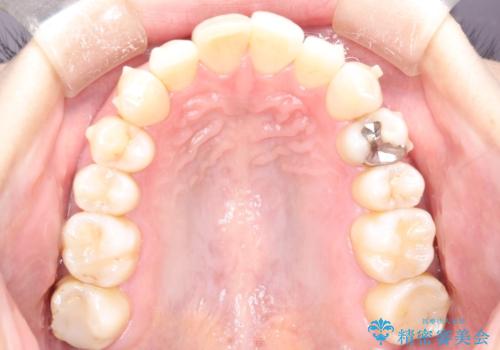

再矯正をインビザラインで目立たず手軽に

- 以前矯正をしていたが、わずかに後戻りをしてしまったのを主訴に来院されました。

装置はなるべくつけたくないとのことで、インビザラインにて治療することとなりました。

- 矯正装置

- インビザラインライト

- 治療期間

- 8ヶ月